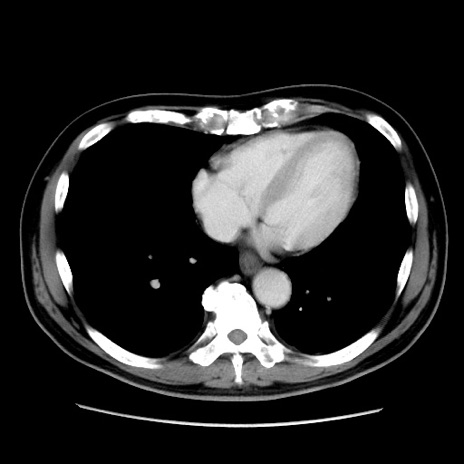

症例16(横断像)

【症例】 70歳代男性

【主訴】 腹痛、嘔吐

【現病歴】 約1ヶ月前より間欠的に腹痛と嘔吐あり、当院消化器内科を受診したところCTで多発する肝臓のLDAを指摘され、精査中であった。以降は消化器症状は安定していたが、2日前より嘔気と腹痛があり、同日より排便・排ガスが消失した。改善認めず、 本日、救急外来を受診した。

【既往歴】 大腸ポリープ切除後。

【身体所見】意識清明・会話良好、BT 36.3℃、BP 127/80mmHg、 P 80bpm、腹部:膨満あり、平坦・軟、上腹部正中および下腹部正中に圧痛あり、反跳痛なし、筋性防御なし。

【データ】WBC 7200、CRP 0.77